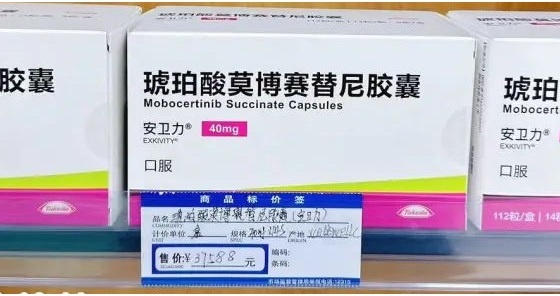

莫博赛替尼(Exkivity)有替代药吗?

Exkivity是一种称为EGFR抑制剂的靶向治疗。它阻断由称为外显子20插入的基因突变引起的异常EGFR蛋白。那么莫博赛替尼(Exkivity)有替代药吗?